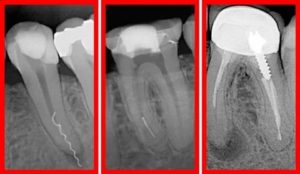

При сохранении боли и дискомфортных ощущений следует обратиться к стоматологу, после рентгена и осмотра пораженного органа начинается лечение. Подробности о симптомах и диагностике пульпита читайте далее.

При повторном обращении производится извлечение пломбы, повторная чистка каналов, болевой синдром исчезает через 1-2 сутки сам по себе. Установка новой пломбы проводится под рентгеном, что позволяет избежать осложнений и развития остаточных воспалительных процессов.

При обращении доктор повторно сделает рентгеновский снимок, который позволит увидеть проблему и решить ее. В случае выдавливания пломбировочного материала проводится полное его извлечение с повторным заполнением полости новым составом.

Неприятные ощущения пройдут спустя 2-3 дня. Перелечивание также осуществляется при неполном заполнении каналов. После устранения материала они заново промываются для устранения инфекции и повторно пломбируются.

В первую очередь врач должен понять, что привело к болезненным ощущениям после удаления нерва. В большинстве случаев ответ на этот вопрос дает рентгеновский снимок: на нем видны и не до конца запломбированные каналы, и перфорация корня, и излишки пломбировочного материала, и обломки эндодонтических инструментов в зубном канале. Если же снимок не показывает никаких врачебных ошибок, значит, имеет место индивидуальная непереносимость пломбировочного материала. - Устранение причины боли

- Повторное пломбирование и контроль

После того, как причина болевых ощущений была найдена и устранена, врач заново проводит стандартные процедуры чистки и обтурации каналов, затем полость зуба закрывается пломбой. Чтобы оценить работу и убедиться в том, что на этот раз все сделано верно, стоматолог может назначить еще один рентген.